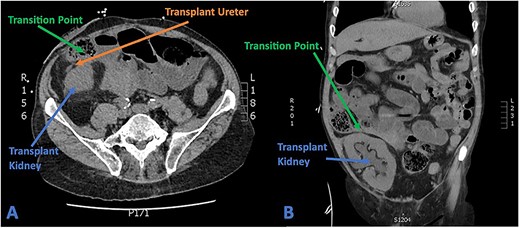

His full blood count and biochemistry showed a significant leucocytosis with a WCC of 36.2 × 109/l, serum lactate of 6.6 mmol/l, and severe decline in renal function as demonstrated by acute rise of serum creatinine to 285 umol/l (baseline 103 umol/l). A subsequent CT scan showed substantial hydronephrosis and hydroureter of the transplanted kidney with distended small bowel loops established in close proximity to the ureteric-ileal conduit anastomosis with an identifiable transition point (Fig. 4). Initial conservative management included copious fluid resuscitation, intravenous antibiotics, and bowel decompression via nasogastric tube. A decision, however, was made for urgent operation when repeated review showed new tachycardia, hypotension, worsening pain with increased analgesic requirements, and generalized peritonism.

(A) Axial CT section showing transplant ureter coursing anterior to kidney transversing over the transition point of SBO. (B) Coronal CT section showing faecalized small bowel approaching transition point with gross hydroureter and hydronephrosis of transplant kidney.

The patient underwent an emergency laparotomy which revealed a transition point caused by significant adhesions of the mid-small bowel that was entrapped between the ileal conduit and its anastomosis to the stretched transplanted ureter. Intraoperative examination showed a grossly dilated ureter with marked tension at the site of small bowel adherence but fortunately no evidence of ischemia. Given the ureteric connection with the ileal conduit, the ureter was anatomically positioned intraperitoneally at the time of operation. Dilated small bowels were encountered proximally with extensive intra-abdominal adhesions but no compromised bowel that required resection.